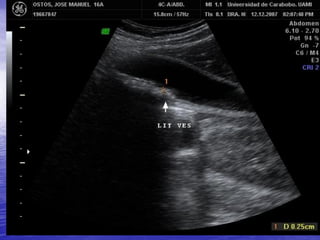

OBSTRUCCION POR LITIASIS

VESICULA BILIAR NO

VISUALIZABLE

EXCLUSION QUIRUGICA / CONTRACCION FISIOLOGICA.

VESICULA ANORMAL:

V.B. CONTRAIDA ALREDEDOR DE UN CALCULO / V.B. EN PORCELANA / COLECISTITIS ENFISEMATOSA.